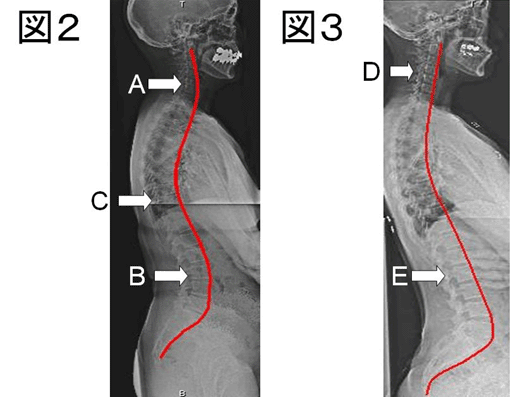

さぁ、ここで心身の健康を保っている方と心身疲労の強い方のレントゲン写真を比較してみましょう。図2は健康な方の背骨のラインです。健康な方は首(図中A)・腰(図中B)は前弯(前に弯曲)しており、その間の胸椎(図中C)は後弯(後ろに弯曲)しているのがお分かりでしょう。

一方、図3は強い肩こり・頭痛と腰痛に悩む患者様の背骨のラインを示します。まず首(図中D)・腰(図中E)を良く見てください。腰も首も前弯が消失し、まっすぐになっているのがわかります。こうなったら、普段の生活も困難なほど、症状が強く出るため、仕事を辞め、治療に専念するしかありません…。当然この患者様は胸椎上下部分全域に渡って叩くと、強い痛みを訴えます。